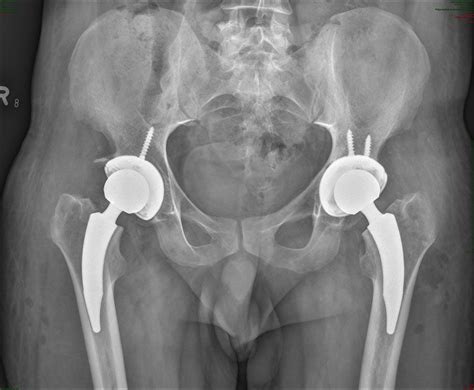

Patients Reporting Groin Pain Post Hip Surgery Demand Better Answers